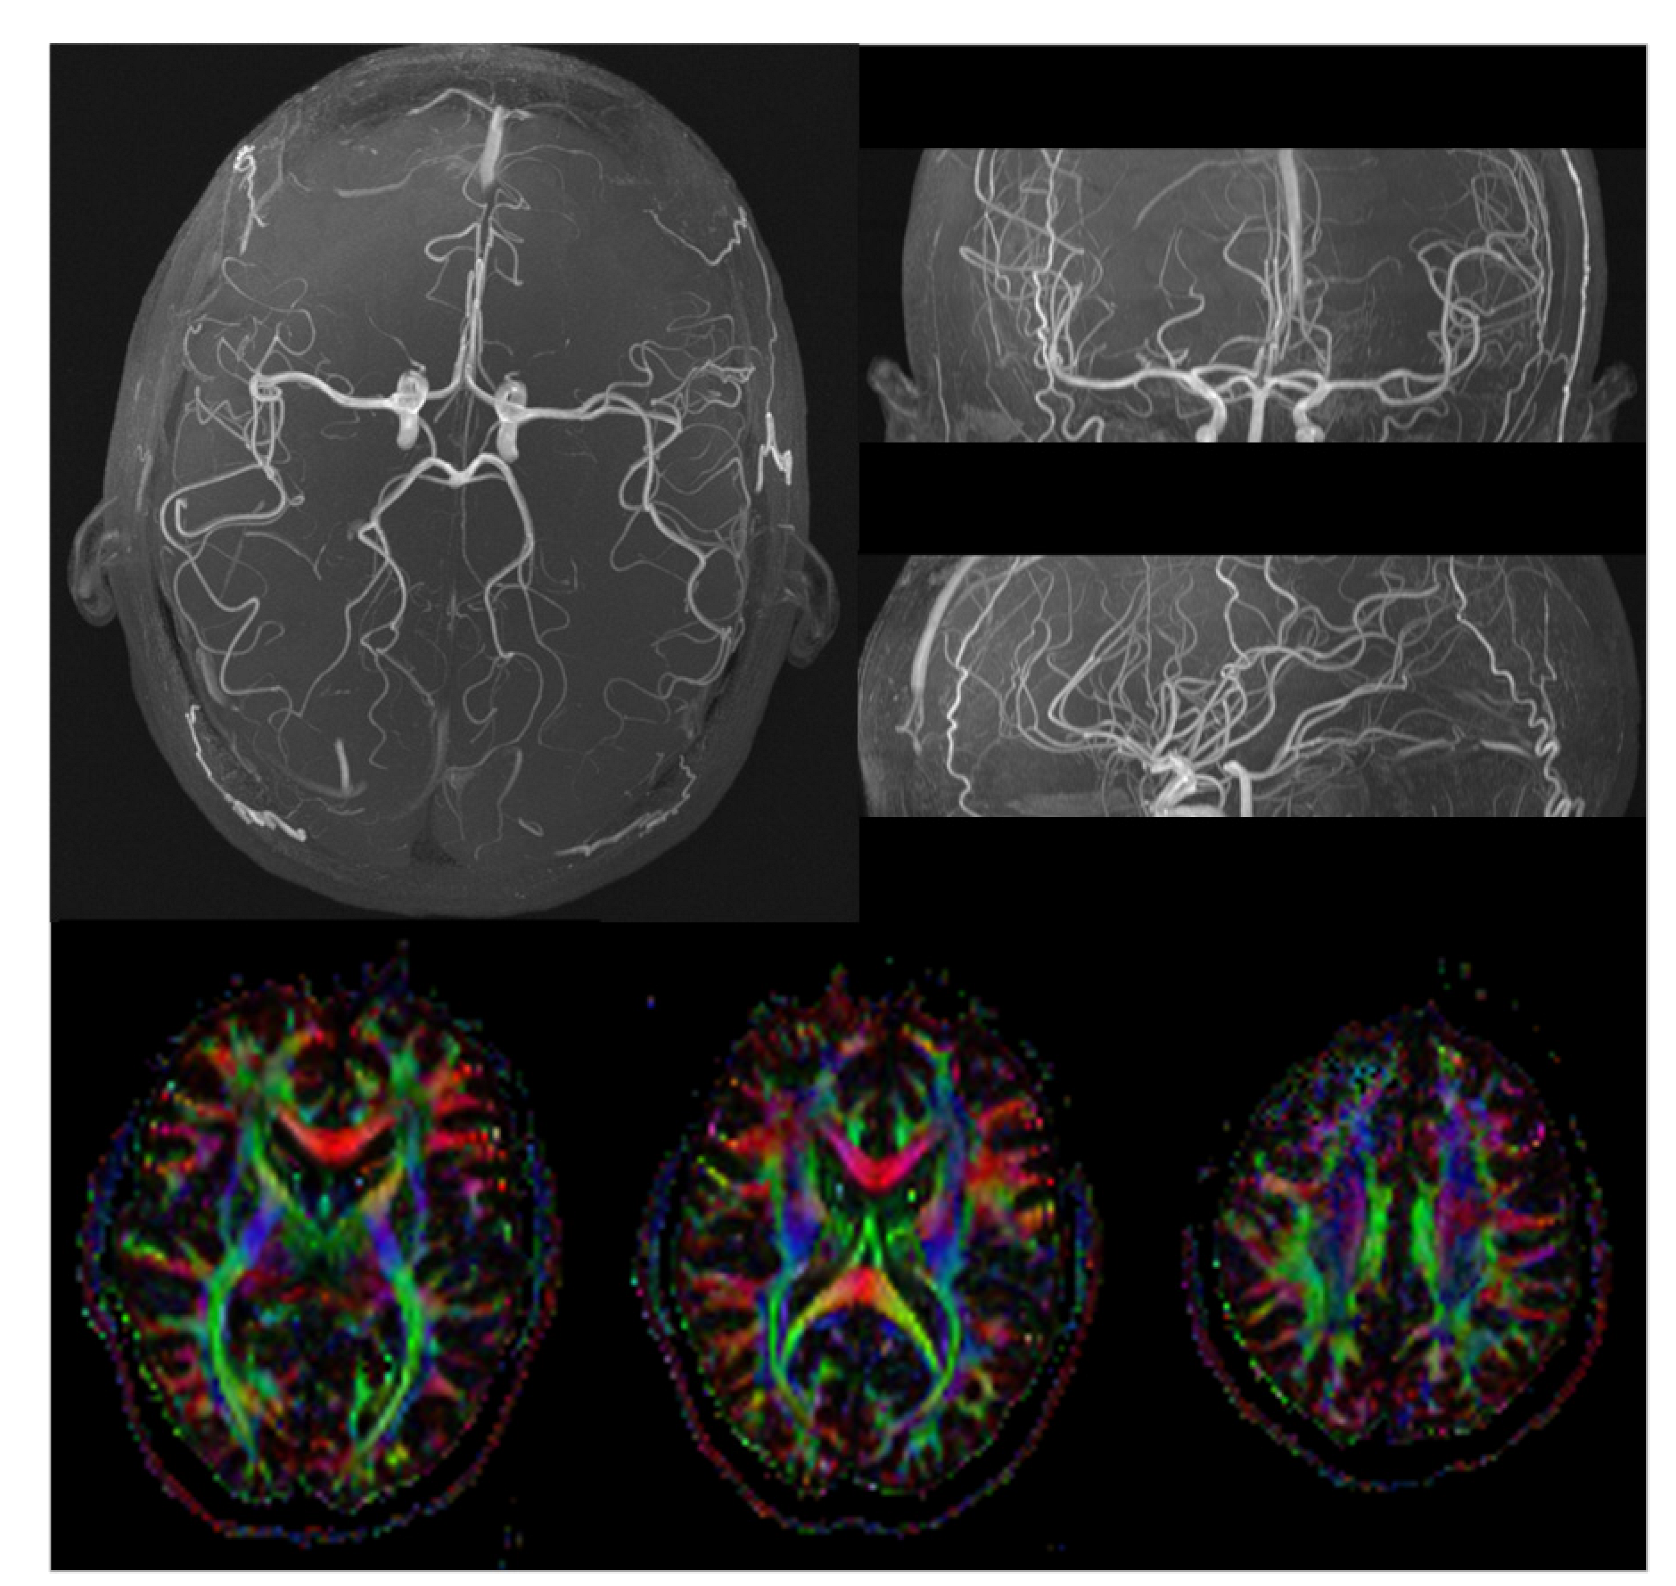

2.3. MRI Imaging

2.3.2. Human Imaging

3. Results